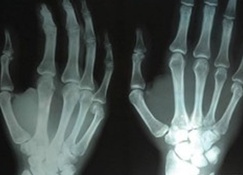

이날 심포지엄은 최근 일본 후쿠시마 원전사고 이후 의료기관에서 사용되는 방사선에 대한 불안감이 증폭되는 상황에서 ‘일반인을 위한 방사선 피폭 - 우리 아이 방사선 검사는 안전할까요?’ 라는 주제로 진행된다.

심포지움은 1부 ‘소아에서의 방사선 검사’, 2부 ‘생활과 방사선 검사’로 구성되며 분야별 전문가의 발표로 진행된다.

특히, 이날 심포지엄에서는 소아 및 임산부 대상 방사선 검사 주의사항, 생활주변 방사선 안전관리 제도 등에 대하여 자세히 설명한다.